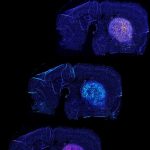

Questa regione che stiamo studiando è chiamata grigio periacqueduttale (PAG) e si trova nel tronco cerebrale, che è molto antico nella storia evolutiva e per questo motivo è funzionalmente simile tra esseri umani e topi”, ha detto l’autore corrispondente Avishek Adhikari, Professore associato di psicologia dell’UCLA. “Anche se le nostre scoperte sono state una sorpresa, è logico che la ricerca del cibo sia radicata in una parte così antica del cervello, dal momento che cercare cibo è qualcosa che tutti gli animali devono fare”.

L’attivazione dell’intera regione PAG provoca una drammatica risposta di panico sia nei topi che negli esseri umani. Ma quando abbiamo stimolato selettivamente solo questo specifico gruppo di neuroni PAG chiamati cellule vgat PAG, queste non hanno alterato la paura, ma hanno invece causato il foraggiamento e l’alimentazione”, ha detto Adhikari.

I ricercatori hanno iniettato nel cervello dei topi un virus geneticamente modificato per far sì che le cellule cerebrali producessero una proteina sensibile alla luce. Quando un laser illumina le cellule tramite un impianto a fibra ottica, la nuova proteina traduce quella luce in attività neurale elettrica nelle cellule. Un microscopio in miniatura, sviluppato all’UCLA e fissato sulla testa del topo, ha registrato l’attività neurale delle cellule.

Quando stimolate con la luce laser, le cellule vgat PAG si attivavano e lanciavano il topo all’inseguimento di grilli vivi e cibo non preda, anche se aveva appena consumato un pasto abbondante. La stimolazione ha anche indotto il topo a seguire oggetti in movimento che non fossero cibo – come palline da ping pong, anche se non ha provato a mangiarle – e ha anche spinto il topo a esplorare con sicurezza tutto ciò che si trovava nel suo recinto.